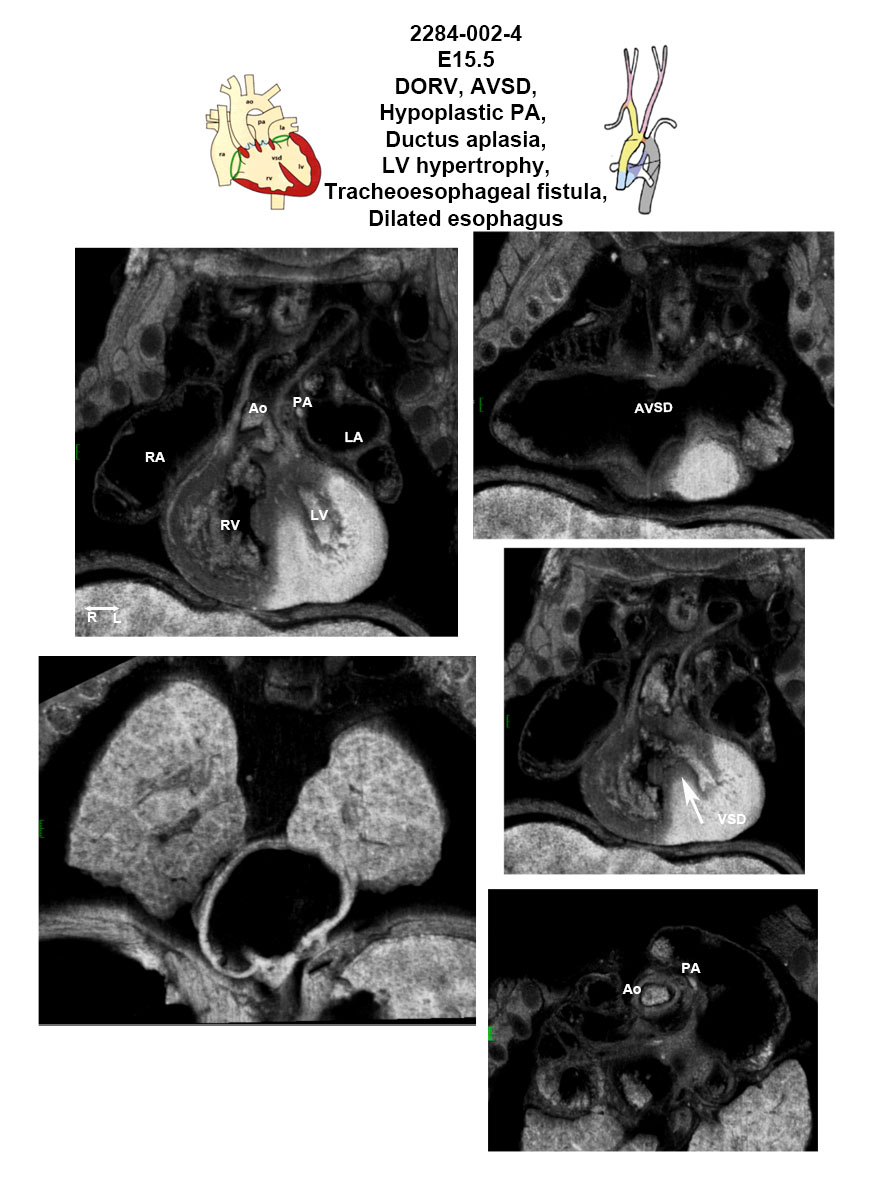

Caption EFIC Summary

Copyright This image is from the Laboratory of Dr. Cecilia Lo, a member of the Cardiovascular Development Consortium (CvDC), Bench to Bassinet (B2B) program of the National Heart Lung and Blood Institute (NHLBI), and is displayed with the permission of the authors. J:175213

Tbc1d32b2b2284Clo TBC1 domain family, member 32; Bench to Bassinet Program (B2B/CVDC), mutation 2284 Cecilia Lo

Tbc1d32b2b2284Clo/Tbc1d32b2b2284Clo C57BL/6J-Tbc1d32b2b2284Clo